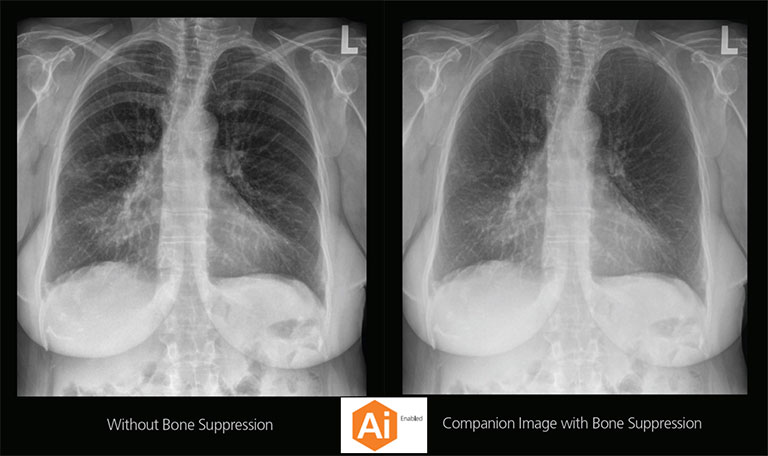

CARESTREAM Image Suite V4 MR11 has set a new standard for workflow efficiency, offering a robust set of features and functionalities to enhance clinical confidence in healthcare professionals. Using an auto-generated companion image from a single exposure, leverage a range of image processing options to increase diagnostic accuracy and enhance patient care.

Our Carestream Focus HD 35/43 Retrofit Detectors, powered by Image Suite Software, are an ideal solution to step up to full digital X-ray for customers who simply cannot compromise on image quality. It seamlessly integrates into existing setups, bringing the power of full digital X-ray with minimal disruption and maximum clarity, along with the following benefits: